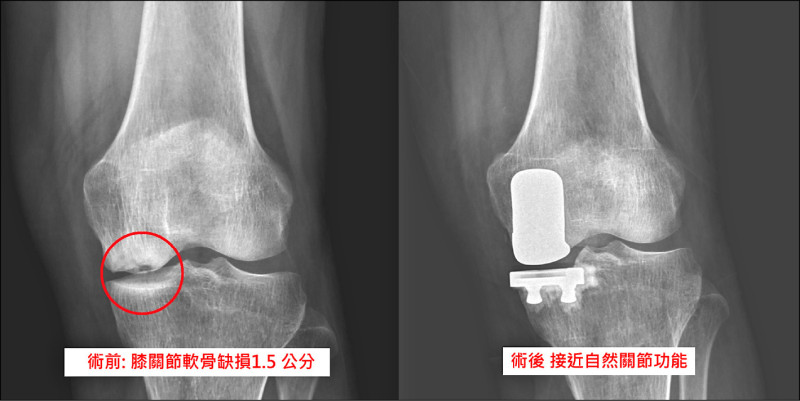

經X光再次評估後,發現她的遠端股骨內側關節面凹了一角,約1.5公分,診斷為「軟骨下不全性骨折合併骨壞死」,合併磁振造影檢查後,發現合併內側半月板後根部斷裂,經過醫病共享決策,接受「半人工膝關節置換手術」,手術約1小時,病患術後隔天即可下床行走,並在3天後順利出院。

以往遇到此病症之患者,手術以全人工膝關節置換為主,但是全人工膝關節置換,相對上切除骨頭及組織較多,造成復原時間較長。此位患者因膝關節外側軟骨無明顯磨損,只需要更換內側半人工膝關節即可,保留其他未受損關節構造,如外側軟骨、前後十字韌帶,不僅讓病人復原速度快,且術後更接近自然關節功能。